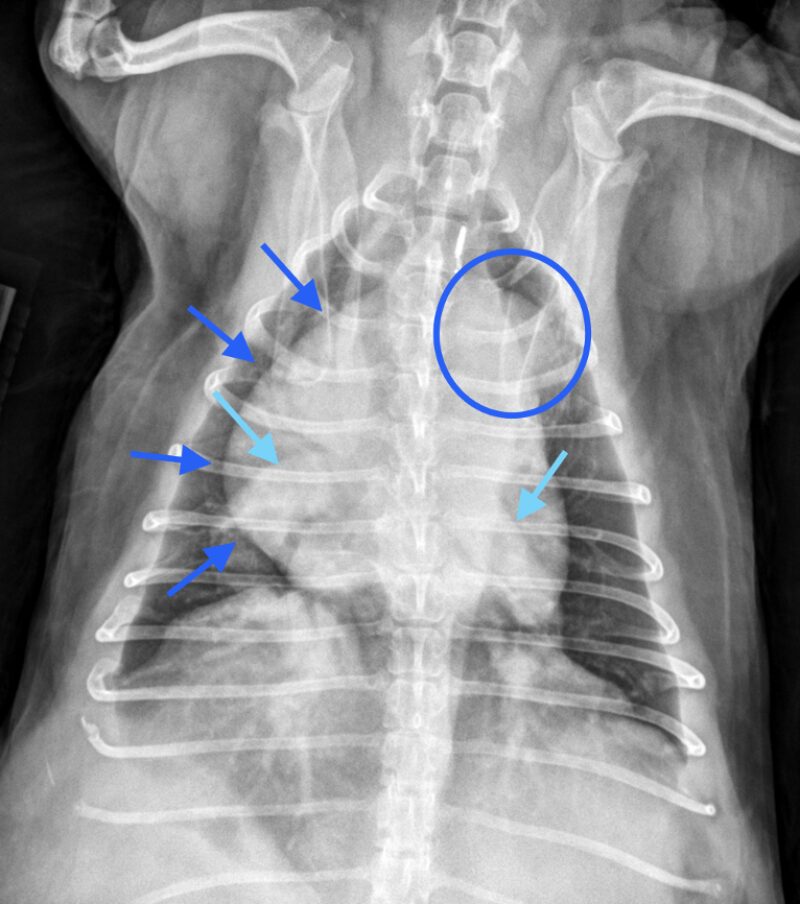

Dr. Anna Adrian, MS, DACVR, antwortet: Vielen Dank für die Zusendung dieses interessanten Falles. Es liegen eine links- und rechtslaterale sowie eine ventrodorsale Thoraxaufnahme vor. In allen drei Projektionen zeigt sich eine ausgeprägte rechtsseitige Kardiomegalie, die mit einer dorsalen Verlagerung der Trachea sowie einem vermehrten Kontakt des Herzens zum Sternum einhergeht (Bild 1, dunkelblaue Pfeilköpfe). In der ventrodorsalen Projektion imponiert die Rechtsherzvergrößerung als typische „reverse D-Form“ (Bild 2, dunkelblaue Pfeile). Zusätzlich fällt in dieser Ansicht auf Höhe der 2-Uhr-Position eine Vorwölbung auf, die einer Dilatation des Truncus pulmonalis entspricht (Bild 2, dunkelblauer Kreis).

Die kaudalen lobären Pulmonalarterien sind hochgradig erweitert, überschreiten deutlich die Breite der 9. Rippe und zeigen einen geschlängelten Verlauf (Bild 1 und 2, hellblaue Pfeile). Zur Erinnerung Venen liegen in der VD-Aufnahme zentral und in der lateralen Aufnahme ventral, wohingegen Arterien lateral und dorsal gelegen sind. Die Vena cava caudalis erscheint geringgradig dilatiert. Das Lungenparenchym weist insgesamt ein leicht- bis mittelgradig ausgeprägtes bronchointerstitielles Muster auf. Im kranialen Abdomen ist eine kraniale abdominale Organomegalie erkennbar, sowie geringgradige Heterogenität des abdominalen Fettgewebes (Bild 1, hellblau gestricheltes Rechteck). Dieser Befund ist vereinbar mit einer Splenomegalie +/- Hepatomegalie und geringgradiger Aszites. Die übrigen abdominalen Strukturen erscheinen unauffällig.

Zusammenfassend liegen eine ausgeprägte rechtsseitige Kardiomegalie sowie eine deutliche Erweiterung der Pulmonalarterien vor. Die Befundkonstellation spricht für eine pulmonale Hypertension in Kombination mit einer Kardiomyopathie, möglicherweise sekundär infolge einer Herzwurmerkrankung oder eines idiopathischen Cor pulmonale. Zur weiterführenden Abklärung wird eine echokardiographische Untersuchung empfohlen. Das bronchointerstitielle Lungenmuster kann altersphysiologisch bedingt sein, differentialdiagnostisch sind jedoch auch eosinophile Infiltrate im Rahmen einer parasitär bedingten Hypersensitivitätsreaktion in Betracht zu ziehen. Die Dilatation der Vena cava caudalis kann einerseits ein Normvariant darstellen, andererseits im Kontext der Rechtsherzvergrößerung auf eine Rechtsherzinsuffizienz oder ein Vena-cava-Syndrom bei hoher parasitärer Last hinweisen.